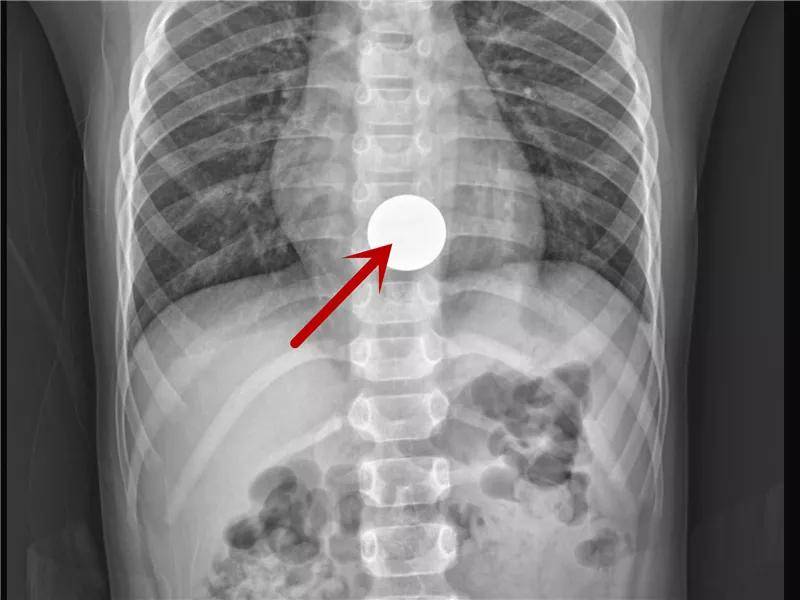

硬币的一场“旅行”

硬币是儿童消化道异物中最最最常见的。虽然有些孩子可以自行排出,但是部分幼龄患儿仍需手术取出。家长还是当心点吧!

进入胃啦